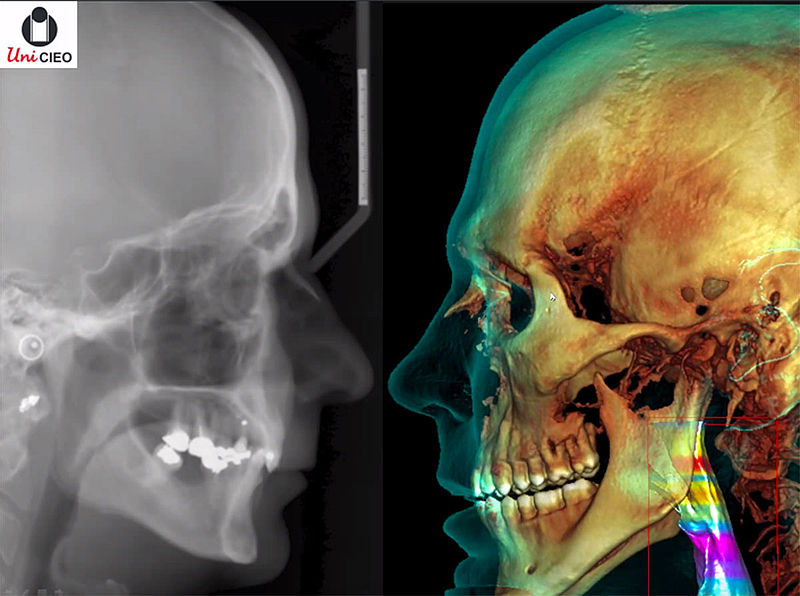

Comparación entre una radiografía clásica y una tomografía

«Por lo general los odontólogos trabajan con imágenes 2D, que son las que se obtienen a través de radiografías panorámicas; sin embargo, como la anatomía humana tienen volumen, la tecnología permite valorar a los pacientes como seres 3D, asimétricos y con características únicas que varían de individuo a individuo», afirma la odontóloga Barrero.

Las imágenes en 2D están compuestas por píxeles que permiten conocer la calidad de la imagen y descomponerla en piezas para un análisis más detallado. Las tomografías, por otro lado, están integradas por unidades denominadas vóxel, los cuales tienen tres dimensiones y definen la resolución de la imagen.